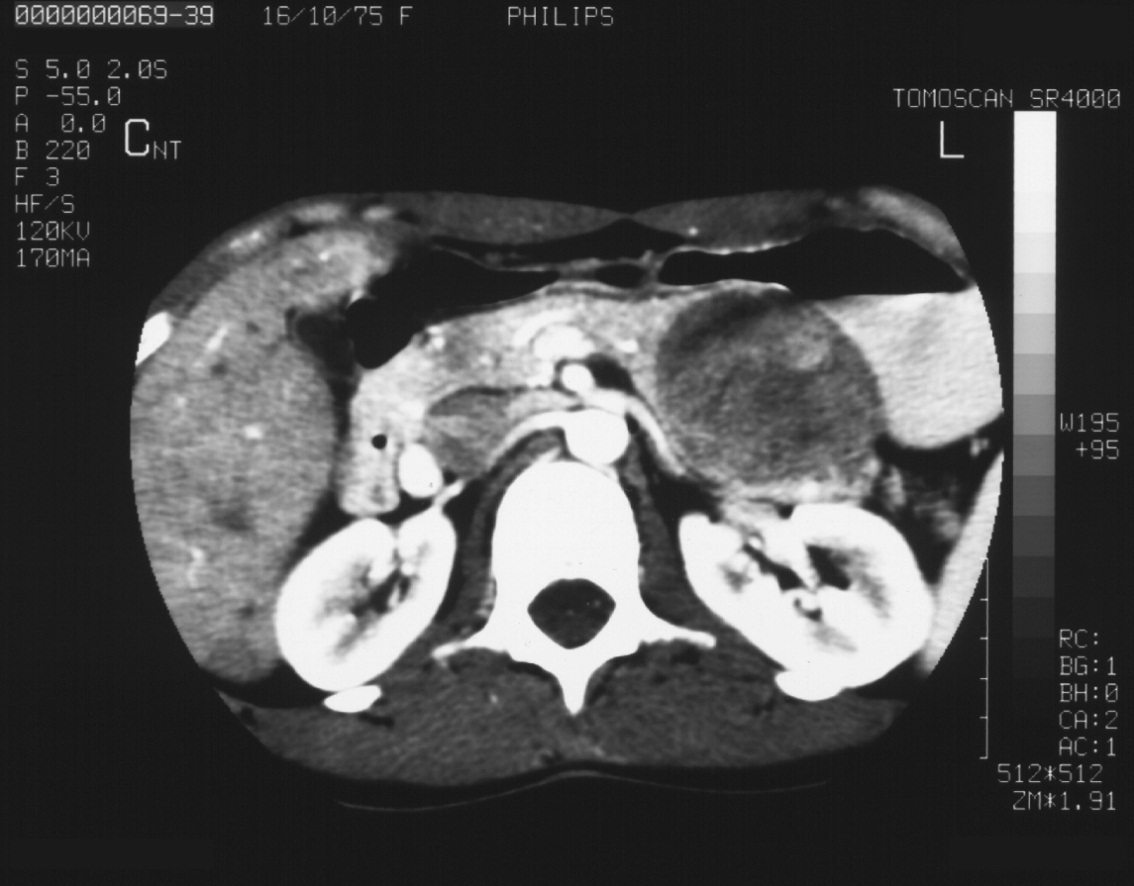

Their US apperarences include mostly an inhomogeneous, hyperechoic or hypoechoic lesion, which is arterially hypervascularised, and several arterioportal shunts may develop. The demonstration of shunt related portal vein flow disturbance by doppler US has a prominent importance. The adjudication of the cirrhosis related HCC by ultrasound is often a particularly difficult task.

HCC appears mostly as low density on the native CT scan, with inhomogeneous structure and a sorrounding with a slightly increased density bearing capsule can be also detected. The completion of the three-phase CT scan (arterial, venous, late) is especially important in case of a suspicion of HCC. The appearance of the inhomogeneous lesion in the arterial phase, including sometimes non contrast enhancing necrotic areas inside, bears with a diagnostic value. The capsule can be detected best in the venous phase.